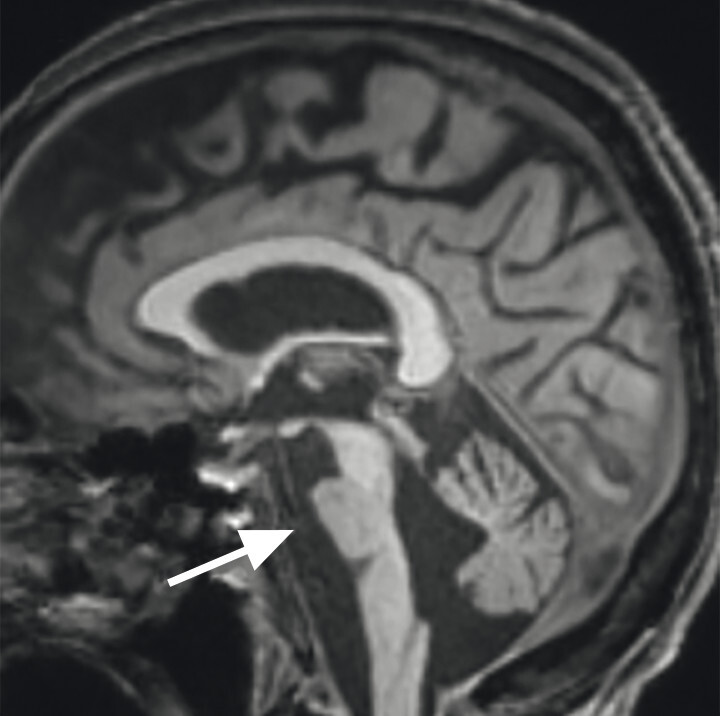

Abb. 69.7 Parkinson-Syndrome: Differenzialdiagnose Multisystematrophie vom zerebellären Prädominanztyp.

67-jährige Patientin mit über Jahre progredienter Verschlechterung des Gleichgewichts, Schluckstörungen und Sprechstörungen. In der T1w 3-D-Sequenz zeigt sich eine ausgeprägte Atrophie des Pons (a, Pfeil), der mittleren Kleinhirnstiele (b, Pfeile) und des Kleinhirns. Diese Veränderungen werden durch die Ganzhirnvolumetrie bestätigt (c): Anomale Regionen der grauen Substanz (mindestens 2 Standardabweichungen unter dem vergleichbaren Volumen des gesunden alters- und geschlechtsgematchten Normkollektivs) sind blau überlagert. Anomale Liquorvolumina (mindestens 2 Standardabweichungen über dem vergleichbaren Volumen des gesunden alters- und geschlechtsgematchten Normkollektivs) sind als rote bis gelbe Überlagerungen auf das individuelle Patientengehirn projiziert. MRT-morphologisch lässt sich somit die Verdachtsdiagnose Multisystematrophie vom zerebellären Prädominanztyp bestätigen.

a Sagittale T1w 3-D-MRT-Sequenz.

b Axiale T1w 3-D-MRT-Sequenz.

c Voxel- und regionenbasierte Analyse.